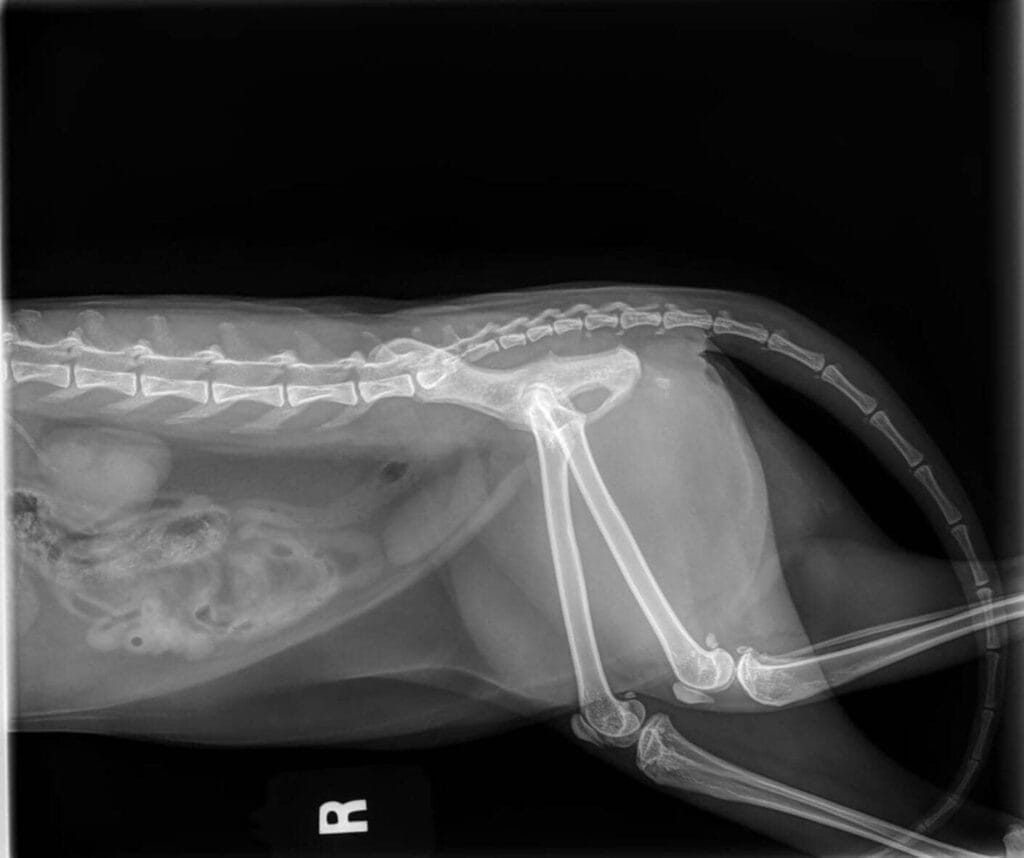

Arthritis in Cats: Spotting the Signs and Supporting Your Feline

As our beloved cats grow older, they can face various health challenges, and arthritis is one of the most common. Did you know that 61% of cats over the age of 6 show signs of arthritis in at least one joint? Since cats are adept at concealing pain, recognising the signs of arthritis early is key to supporting their well-being.